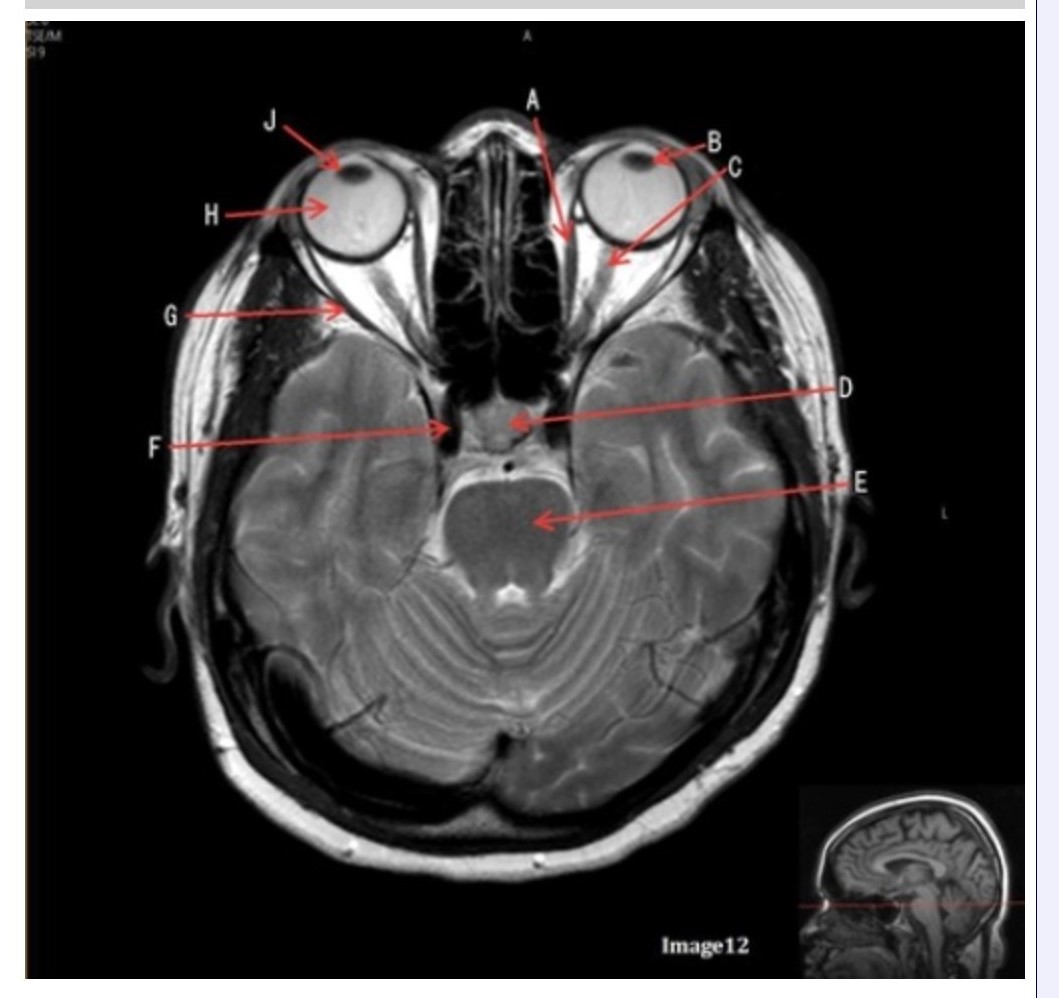

Letter H in Image 12 is pointing to:

A. Lens

B. Lateral rectus muscle

C. Medial rectus muscle

D. Internal carotid artery

E. Globe

Letter B in Image 12 is pointing to:

A. Left optic nerve

B. Lateral rectus muscle

C. Medial rectus muscle

D. Lens

E. Midbrain

Letter J in Image 12 is pointing to:

A. Globe

B. Lateral rectus muscle

C. Medial rectus muscle

D. Right lens

E. Left lens

Letter F in Image 12 is pointing to:

A. Lens

B. Lateral rectus muscle

C. Medial rectus muscle

D. Internal carotid artery

E. Globe

Letter C in Image 12 is pointing to:

A. Left optic nerve

B. Lateral rectus muscle

C. Medial rectus muscle

D. Lens

E. Midbrain

Letter D in Image 12 is pointing to:

A. Optic nerve

B. Pituitary gland

C. Globe

D. Lens

E. Midbrain

Letter G in Image 12 is pointing to:

A. Lens

B. Lateral rectus muscle

C. Medial rectus muscle

D. Internal carotid artery

E. Globe

Letter E in Image 12 is pointing to:

A. Optic nerve

B. Pituitary gland

C. Globe

D. Pons

E. Left lens